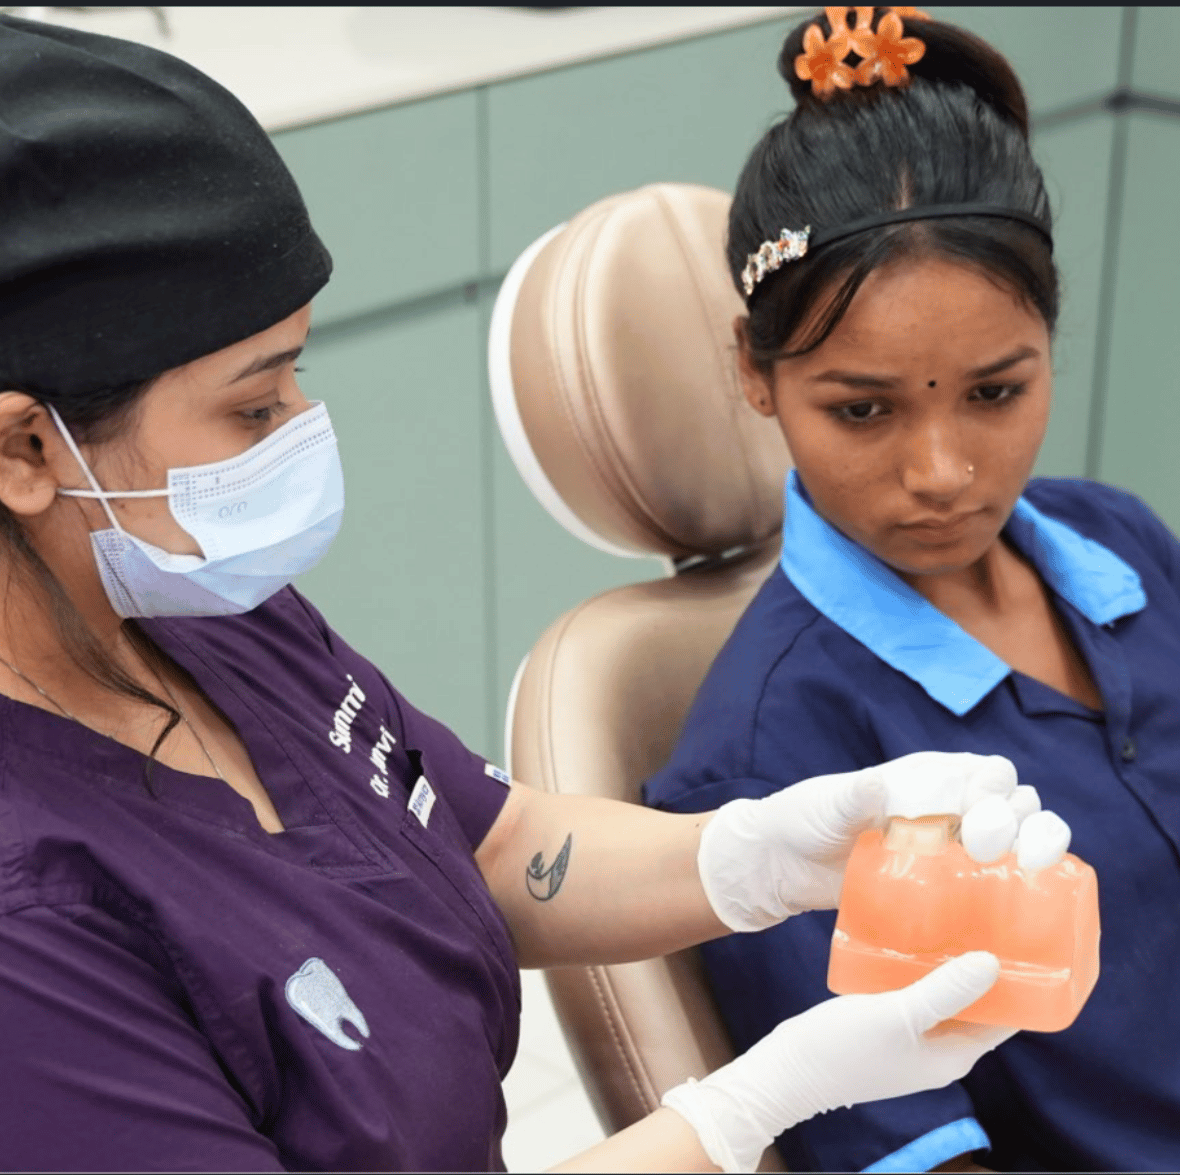

At Summirow Dental Care Hospital, we believe a strong smile builds strong confidence. If you have a damaged, weak, or missing tooth, our advanced Dental Crowns and Bridges in Surat are designed to restore both function and aesthetics, seamlessly and comfortably.

A Dental Crown is a custom-designed cap that completely covers and protects a damaged or weakened tooth, restoring its strength, shape, size, appearance, and proper bite function.

At Summirow Dental Care Hospital, we carefully design each crown to match the natural color and contour of your existing teeth, ensuring it blends seamlessly with your smile while providing long-lasting durability and comfort.

At Summirow Dental Care Hospital, we craft crowns that blend perfectly with your natural teeth, so no one can tell the difference.